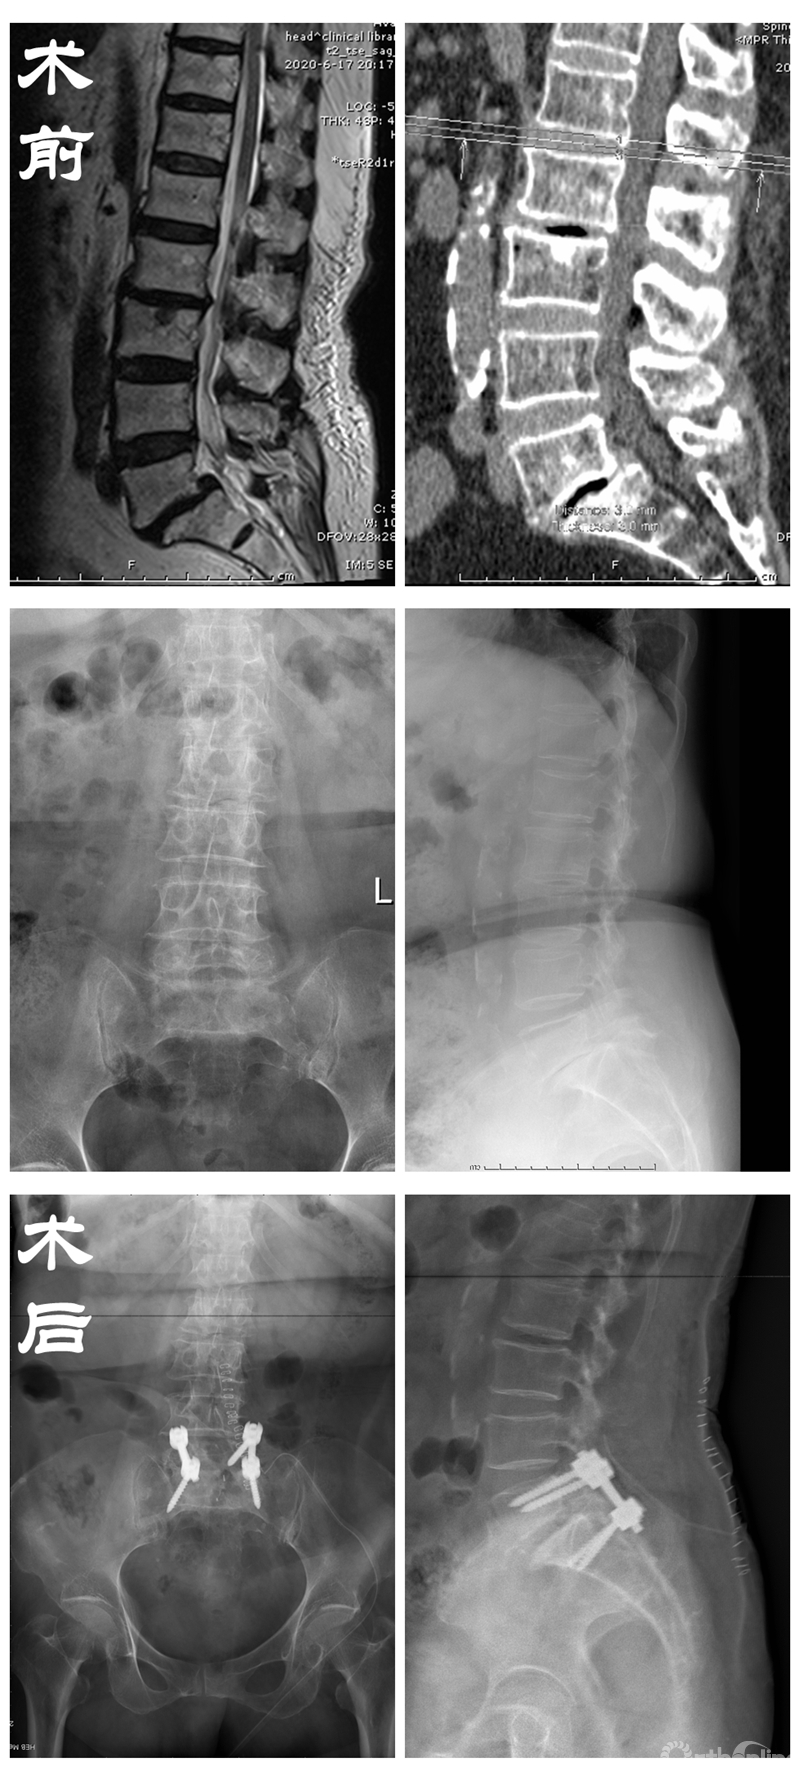

医疗技术的发展也为老龄化社会带来了翻天覆地的变化。85岁王奶奶患有的腰椎滑脱症多年,常常因此痛不欲生。众所周知,对于80岁以上的高龄患者进行手术本身风险就很高,医生的原则是能保守就不开刀。

在备受折磨的患者苦苦央求下,丁文元教授为解决患者病痛,立即召集多科室进行会诊,在确认患者的心、肺、脑功能可以负担手术及麻醉后,为患者进行了腰椎切开复位固定融合术,术后患者腰腿疼缓解,日常活动均可自理。

患者资料